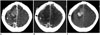

In the head region, dual-energy iodine map is useful for differentiating between tumor bleeding and pure intracerebral hemorrhage (Fig. 9) or between contrast extravasation and intracerebral hemorrhage after intra-arterial revascularization in patients with acute ischemic stroke (32, 33).